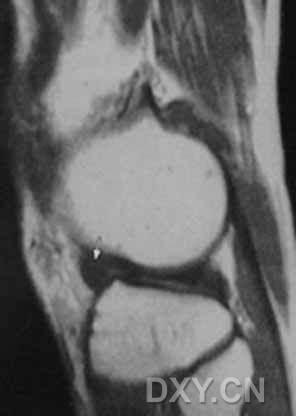

| 0级 外侧半月板表现为均匀低信号,形态规则